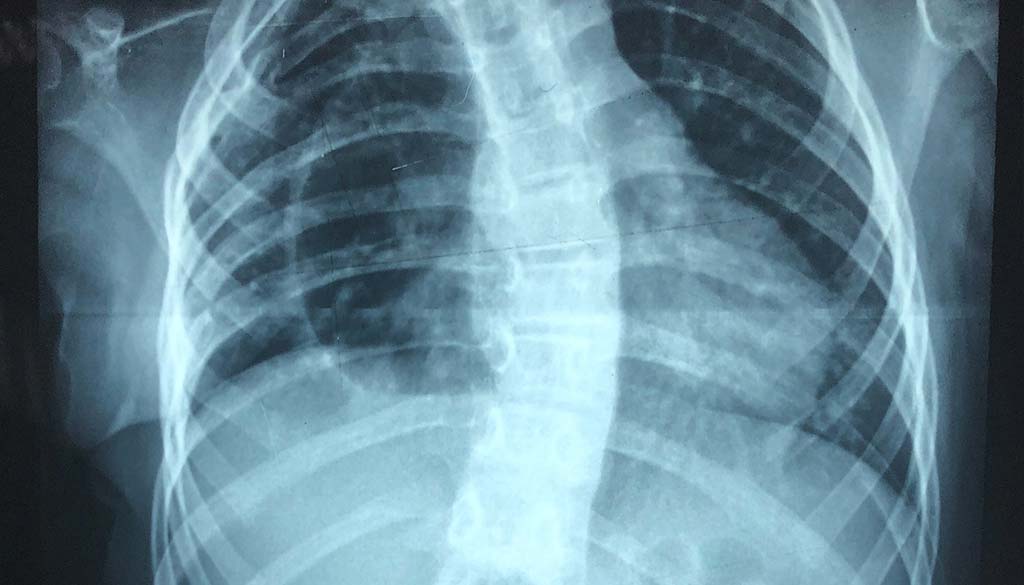

For those who have the device, the FDA did not recommend its removal if it had been functioning properly. However, if patients experience unexpected back pain with the device, additional testing, including x-rays, should be done to evaluate the situation.